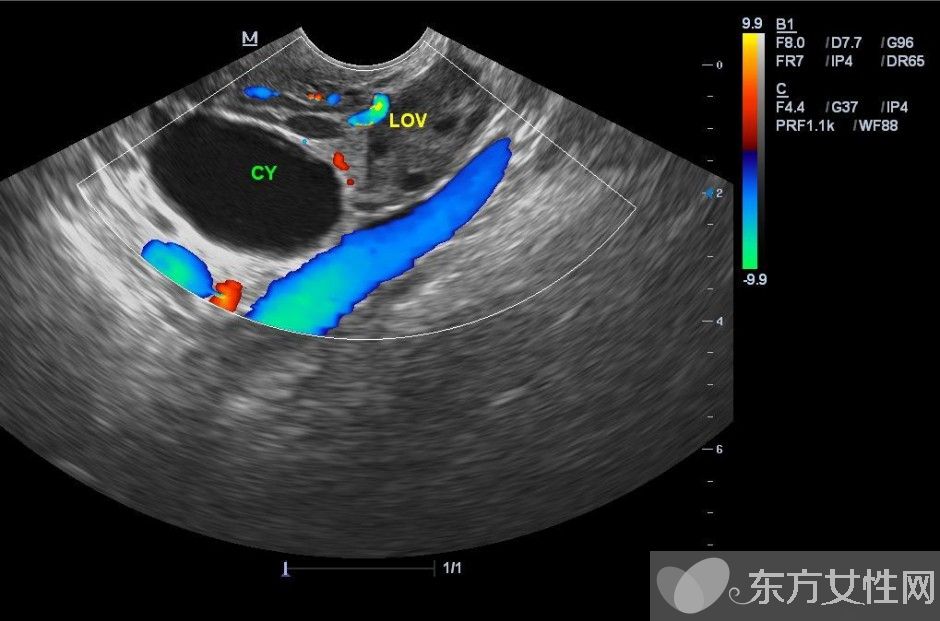

卵巢囊腫是指卵巢上長(zhǎng)出的囊性腫物,有各種不同的性質(zhì)和形態(tài),如單一型或混合型、一側(cè)性或雙側(cè)性、囊性或?qū)嵸|(zhì)性、良性或惡性。通常可分為兩大類:

如果卵巢囊腫經(jīng)隨診沒有縮小或反而增大(直徑大于6厘米)以及青春期前的女孩和絕經(jīng)后的婦女出現(xiàn)的囊腫,應(yīng)懷疑卵巢腫瘤的可能,往往需要借助于進(jìn)一步的輔助檢查,甚至手術(shù)來(lái)診斷和治療。卵巢腫瘤常常會(huì)引起痛經(jīng)、月經(jīng)失調(diào)、性交痛等癥狀,甚至導(dǎo)致不孕。